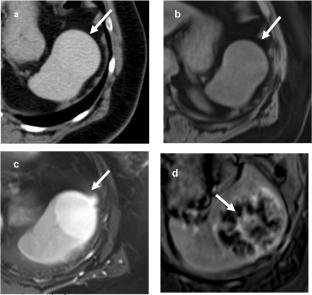

脾的横断面介入放射学(CSIR)在过去的二十年中得到了发展。当代数据显示,CT和us引导下的脾手术比以前认为的更安全,允许在临床适当时进行活检和引流。然而,在干预之前,需要对脾脏病变进行密切的影像学评估,以识别明确的良性,“不要触摸”病变以及可能需要活检的可疑特征。本文将首先关注脾病变的影像学检查和决策,然后讨论现代CSIR技术以最大限度地提高安全性和产出率。

Cross-sectional interventional radiology (CSIR) for the spleen has evolved over the past two decades. Contemporary data show that CT- and US-guided splenic procedures are safer than once assumed, allowing for biopsy and drainage when clinically appropriate. Prior to intervention, however, close imaging evaluation of splenic lesions is required in order to recognize definitively benign, “do not touch” lesions as well as suspicious features that might warrant biopsy. This manuscript will first focus on imaging workup and decision-making for splenic lesions, and then discuss modern CSIR techniques to maximize both safety and yield.